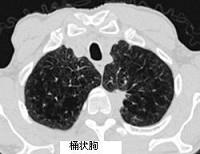

关于阻塞性肺气肿的体征,下列错误的是 ( )A、心浊音界缩小B、听诊呼吸音减弱C、触诊语颤增强D、胸部叩诊呈过清音E、桶状胸

选项 A、心浊音界缩小 B、听诊呼吸音减弱 C、触诊语颤增强 D、胸部叩诊呈过清音 E、桶状胸

答案 C